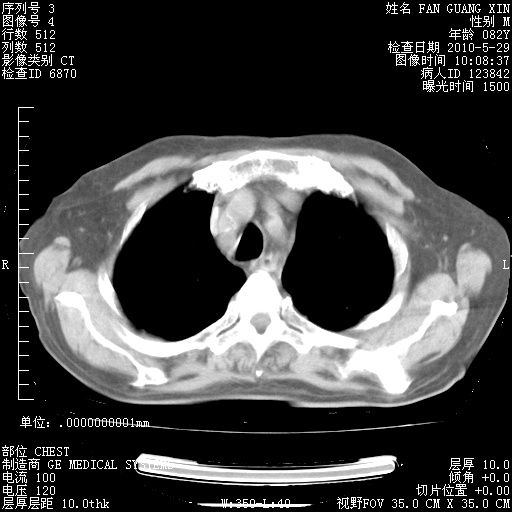

再治疗10天后的肺部CT

再治疗10天后的肺部CT 纵膈窗

阅读此次胸部CT,肺间质渗出性改变较入院时有吸收。目前从体温、白细胞、中性分叶明显增高,肯定存在细菌感染(发生医院感染哦,若无消化道及泌尿系统等感染的依据,肺部感染可能大)。若你院头孢哌酮舒巴坦钠耐药率较高,同意你的方案,若48小时体温仍高,可考虑使用碳青霉稀类抗菌药物,同时可予超声雾化、注意滴数时加大液体量。白蛋白33.30g/L较低哦,需加强营养等支持治疗。